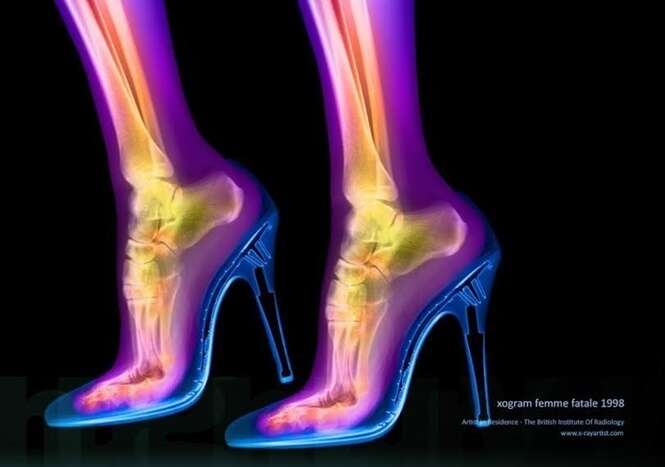

10 exames de raio-X feitos em pacientes que se deram mal tentando conseguir prazer íntimo

As imagens que você verá a seguir mostram exames de raio-X que são um tanto quanto incomuns.

Os exames mostram objetos pra lá de inusitados inseridos dentro dos corpos de pacientes de várias partes do mundo.

Todos eles certamente farão você estremecer de dor.

Os pacientes certamente tentaram usar tais itens para se dar prazer íntimo, mas acabaram se dando muito mal.